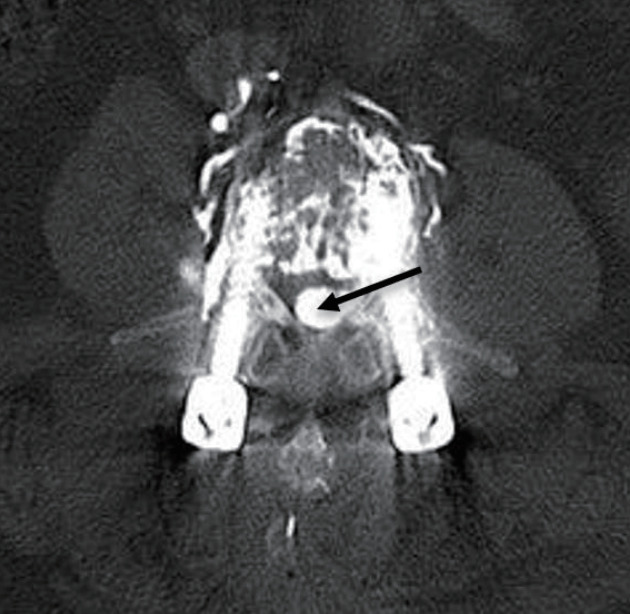

骨水泥增强椎弓根螺钉内固定是一种被广泛接受的治疗骨质疏松性骨折的方法,但它具有固有的风险,特别是与骨水泥泄漏和栓塞有关。本研究旨在分析一例水泥内固定术后并发症的临床病例,并对相关文献进行详细的复习。一名70岁的患者接受了L2-L4椎弓根螺钉内固定和聚甲基丙烯酸甲酯增强,导致水泥渗漏到椎管中并随后发生肺栓塞。经翻修手术和栓塞保守治疗后,患者病情稳定,表明保守治疗水泥栓塞是有效的。为了补充本病例,我们进行了全面的文献回顾,以探讨与骨水泥增强术相关的并发症的原因、预防和治疗。研究结果表明,尽管骨水泥增强椎弓根螺钉内固定仍然是治疗骨质疏松性骨折的主要技术,但通过适当的治疗方案,相关风险是可控的。本研究通过强调与骨水泥固定相关的风险和解决方案,从而有助于改善患者的预后和制定标准化的治疗指南,对医疗保健专业人员具有实际意义。

Cement-augmented pedicle screw instrumentation is a widely accepted method for managing osteoporotic fractures, but it carries inherent risks, particularly related to cement leakage and embolism. This study aimed to analyze a clinical case of complications following cement fixation and provide a detailed review of relevant literature. A 70-year-old patient underwent transpedicular screw instrumentation from L2-L4 with polymethyl methacrylate augmentation, which resulted in cement leakage into the spinal canal and subsequent pulmonary embolism. After revision surgery and conservative treatment for the embolism, the patient's condition stabilized, demonstrating that conservative measures can be effective in managing cement embolism. To complement this case, a comprehensive literature review was conducted to explore the causes, prevention, and treatment of complications related to cement augmentation. The findings support that while cement-augmented pedicle screw instrumentation remains a leading technique for osteoporotic fractures, the associated risks are manageable with proper treatment protocols. This study holds practical significance for healthcare professionals by highlighting both the risks and solutions associated with cement fixation, thus contributing to improved patient outcomes and the development of standardized treatment guidelines.